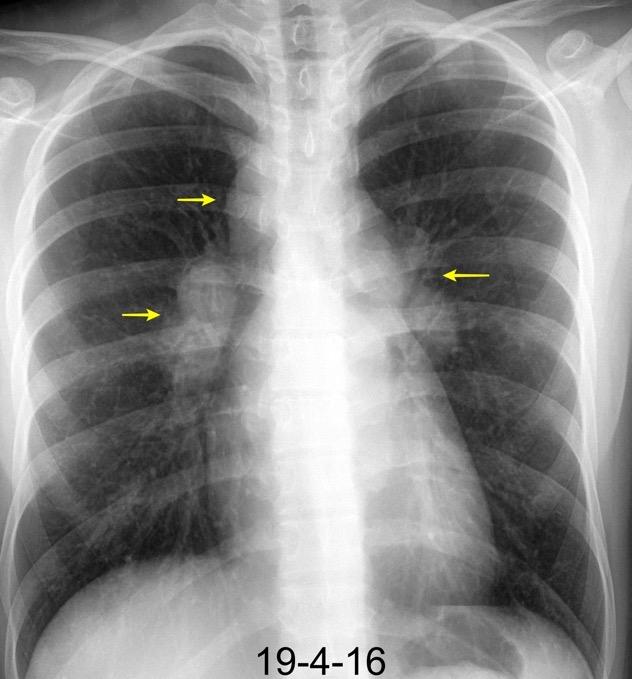

En el normal, el bronquio intermediario (BI) aparece en la proyección lateral, como una línea fina vertical que cruza el bronquio del LSI en su unión con el principal. (BPI) Engrosamiento del bronquio intermediario (BI)

97% de normales

Causas

Fallo cardiaco

Ca de pulmón

Metástasis

Linfoma

Sarcoidosis

Castleman

Schnur MJ et al.. Thickening of the Posterior Wall of the Bronchus Intermedius. Radiology. 1981

MJ et al.. Thickening of the Posterior Wall of the Bronchus Intermedius. Radiology. 1981 Ca. microcítico